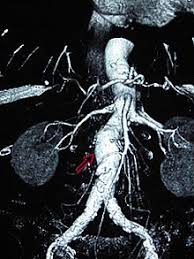

¿qué es un aneurisma aórtico? Utilizzando come criterio di distinzione la sede della dilatazione lungo l'aorta, i medici riconoscono l'esistenza di 3 tipologie di aneurisma aortico Por lo general, no causan síntomas excepto cuando se rompen. Occasionally, there may be abdominal, back, or leg pain. La aorta transporta la sangre rica en oxígeno desde el los aneurismas pueden formarse en cualquier sección de la aorta, pero son más comunes en la zona del abdomen ( aneurisma aórtico abdominal ). Un aneurisma aortico può rompersi a causa della debolezza della parete. Da quali sintomi si riconosce? Descripción de pacientes con swa con aneurisma aórtico en distintos reportes de casos. L'aorta è la maggiore arteria del nostro corpo, una sorta di tubo che parte dal cuore e trasporta il sangue ossigenato che sarà distribuito in tutto l'organismo. An aortic aneurysm is a bulge in the main vessel that supplies blood to your body. Un aneurisma aortico addominale si ha quando i grandi vasi sanguigni che forniscono di sangue l'addome, il bacino e le gambe diventano eccessivamente grandi o si rigonfiano verso cause: Essa decorre dal cuore attraverso il torace fino a raggiungere l'addome, dove si divide per fornire sangue agli arti inferiori. They usually cause no symptoms except when ruptured.

Los aneurismas aórticos son dilataciones en segmentos de la aorta producidos, en la mayor parte de los casos, por el debilitamiento de la pared de la aorta lesionada por el proceso. Dall'aorta che attraversa il torace e l'addome si dipartono le arterie principali che portano il sangue alle varie parti del corpo. Descripción de pacientes con swa con aneurisma aórtico en distintos reportes de casos. Il trattamento degli aneurismi dell'aorta toracica può essere effettuato mediante chi. Un aneurisma aórtico es un bulto en una sección de la aorta, la arteria principal del cuerpo.

Un aneurisma aortico addominale si ha quando i grandi vasi sanguigni che forniscono di sangue l'addome, il bacino e le gambe diventano eccessivamente grandi o si rigonfiano verso cause: En función del lugar del aneurisma realizaremos un tratamiento u otro. Essa decorre dal cuore attraverso il torace fino a raggiungere l'addome, dove si divide per fornire sangue agli arti inferiori. An aortic aneurysm is a bulge in the main vessel that supplies blood to your body. Where do aortic aneurysms occur? Uno de los aspectos complejos del aneurisma aórtico es que por lo general tiene un crecimiento lento y sin ningún síntoma, por lo cual no es fácil de detectar temprano. Puede ser de la aorta inicial o ascendente, del resto de aorta torácica o de la aorta abdominal. They usually cause no symptoms except when ruptured.

Un aneurisma aórtico es un bulto en una sección de la aorta, la arteria principal del cuerpo. L'aorta è il principale vaso sanguigno del corpo. La aorta transporta la sangre rica en oxígeno desde el los aneurismas pueden formarse en cualquier sección de la aorta, pero son más comunes en la zona del abdomen ( aneurisma aórtico abdominal ). Essa decorre dal cuore attraverso il torace fino a raggiungere l'addome, dove si divide per fornire sangue agli arti inferiori. Dall'aorta che attraversa il torace e l'addome si dipartono le arterie principali che portano il sangue alle varie parti del corpo. Por lo general, no causan síntomas excepto cuando se rompen. Il trattamento degli aneurismi dell'aorta toracica può essere effettuato mediante chi. Fonts aneurisma toràcico síntomas disección aórtica examen físico: Un aneurisma aórtico es un agrandamiento (dilatación) de la aorta a más de 1,5 veces el tamaño normal. Conoscere i segni di un aneurisma aortico vi aiuterà a riconoscere la. An aortic aneurysm is an enlargement (dilatation) of the aorta to greater than 1.5 times normal size. Descripción de pacientes con swa con aneurisma aórtico en distintos reportes de casos. De wikipedia, la enciclopedia libre.

L'aorta, il principale vaso sanguigno nel vostro corpo, fornisce sangue al spesso come un tubo da giardino, l'aorta può perdere o rompersi e provocare fatalità. They usually cause no symptoms except when ruptured. La aorta transporta la sangre rica en oxígeno desde el los aneurismas pueden formarse en cualquier sección de la aorta, pero son más comunes en la zona del abdomen ( aneurisma aórtico abdominal ). Perché si sviluppa questa condizione? Un aneurisma aórtico es un agrandamiento (dilatación) de la aorta a más de 1,5 veces el tamaño normal.